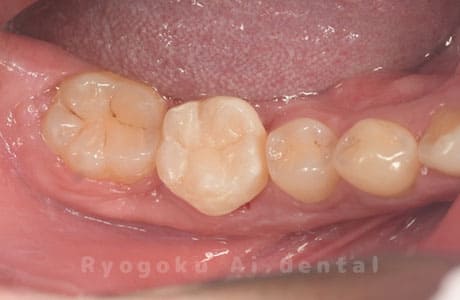

Case27

-

重度カリエス

歯牙移植咬合面術前 -

移植する親知らず

歯牙移植術直後咬合面

歯牙移植術後咬合面

歯牙移植術前側面

歯牙移植術中側面

歯牙移植術後側面

- 原因

- 重度カリエス

- 治療内容

- 自家歯牙移植、部分矯正

- 治療費用

- 220,000円(移植費用)

110,000円(部分矯正費用)

虫歯が大きく、保存不可能となった歯を上の親知らずと交換する自家歯牙移植を行いました。移植歯が小ぶりであったため、部分矯正を行い問題なく噛み合い、経過良好です。